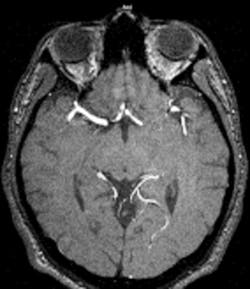

Higher Signal to Noise Ration – More Sensitive

Higher Image Contrast in soft tissue

Overall higher image quality

In short it appears that 3T MRI Systems are not just stronger but also more efficient and more equipped to adapt to the future demands of MRI exams. A name brand MRI vendor told me 3T scanners can perform routine MRI scans and add value by creating and handling additional volume with newer offerings such as breast MRI, MR angiography and cardiac scanning which makes them more valuable than a 1.5T system.